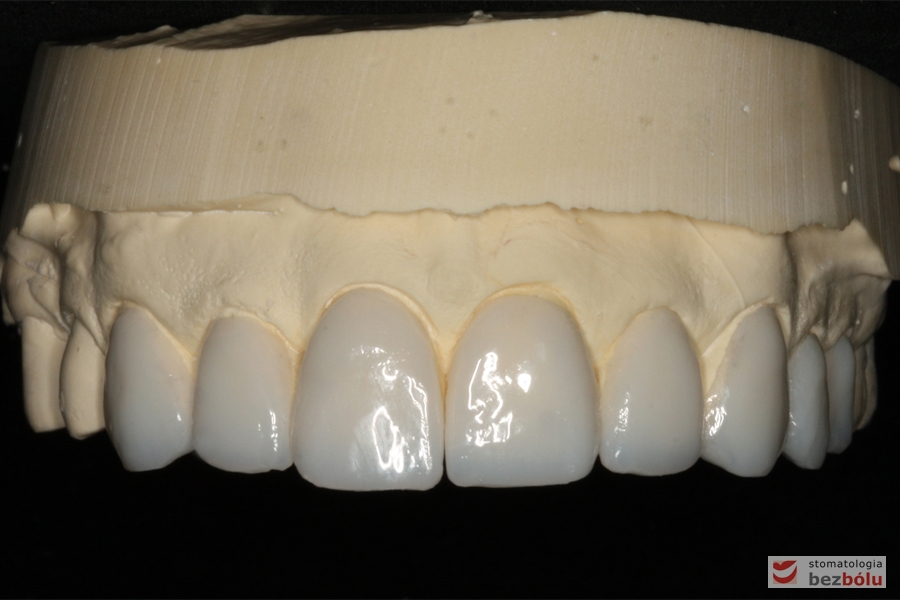

Wizualizacja docelowej odbudowy protetycznej - wax-up

Wizualizacja docelowej odbudowy protetycznej – wax-up

Ostateczne całoceramiczne licówki wykonane w systemie e-max